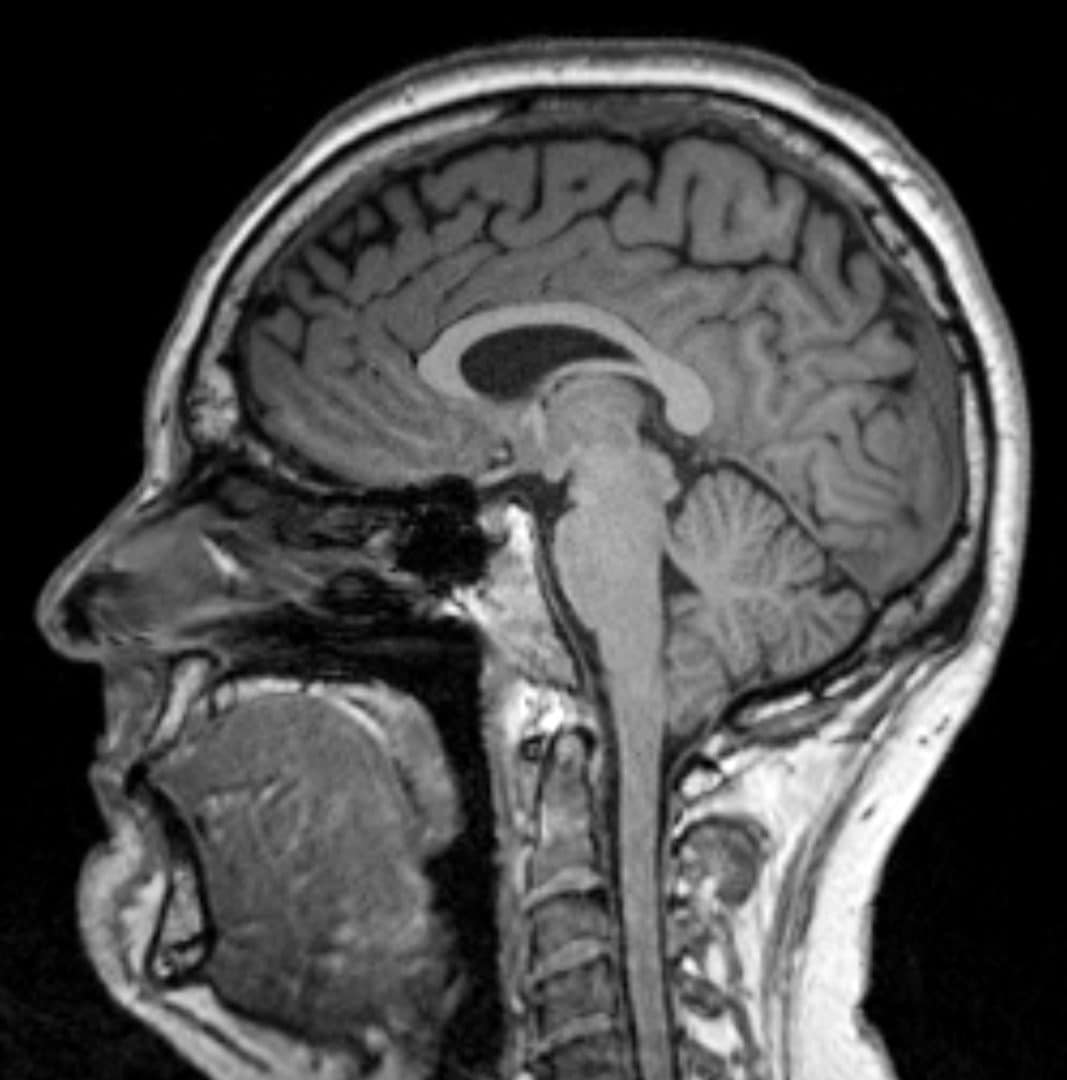

Tomography aims to reveal the internal structure of a patient based on X-ray images taken from different directions. The resulting slice image is formed with a mathematical algorithm. I am a professional mathematician studying inverse problems of medical imaging. In this video I explain how the tomographic image is calculated. The explanation is visual and aimed at a general audience.

What is tomography?